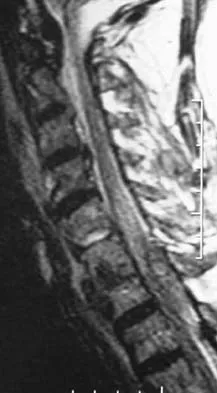

A 65-year-old man with ankylosing spondylitis has neck pain after falling back over his lawnmower, striking his thoracic spine, and forcing his neck into extension. Examination reveals subtle weakness of the intrinsics and finger flexors at approximately 4+/5. Initial management consists of immobilization in a rigid collar, and placing his head in the anatomic position. Radiographs reveal a subtle extension fracture of the lower cervical spine. Approximately 6 hours after the injury, he reports increasing paresthesias in his upper and lower extremities, and examination now shows his intrinsics are 2/5, finger flexors are 3/5, and his triceps are now weak at 4/5 on manual motor testing. In addition, his lower extremities now show weakness in both dorsal and plantar flexion of the ankle in the range of 4/5. Repeat radiographs appear unchanged. An MRI scan is shown in Figure 2. Management should now consist of

Explanation

It is not uncommon for patients with ankylosing spondylitis to sustain extension-type fractures, most typically of the cervicothoracic junction. These fractures can appear nondisplaced or minimally displaced initially, making them difficult to diagnose. Because there is no mobility between vertebrae, fractures tend to occur more like those of a transverse fracture of a long bone. In addition, the vertebral bodies are vascular and their canals are relatively enclosed, making them vulnerable to epidural bleeding. The MRI scan reveals an epidural hematoma located posteriorly on the cord; therefore, the treatment of choice is surgical evacuation and a posterior laminectomy. Because of the intrinsic instability of such fractures at the time of the laminectomy, internal fixation and stabilization with a posterior fusion is warranted. A simple laminectomy will only increase instability, and control is unlikely with halo vest immobilization. An anterior procedure will not effectively treat the problem given the location of the hematoma. Consideration can be given to methylprednisolone and observation; however, this will not eradicate the problem. Bohlman HH: Acute fractures and dislocations of the cervical spine. J Bone Joint Surg Am 1979;61:1119-1142.